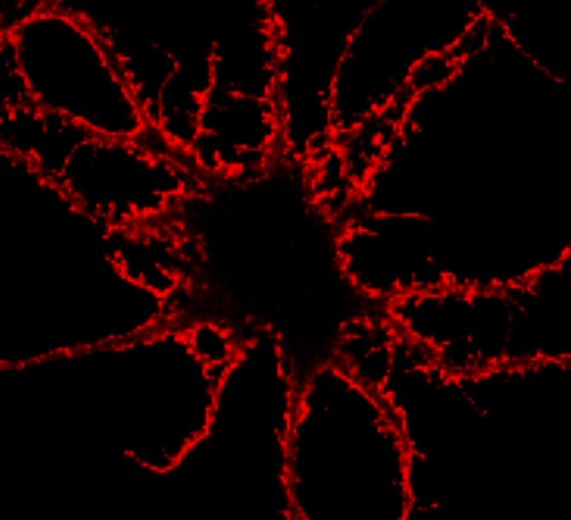

Se ha descubierto que una proteína de la que ya se sabía que puede activarse para proteger a las células nerviosas frente a los daños producidos durante un fallo cardíaco o un ataque de epilepsia, también desempeña otra función importante: Regula la transferencia de información entre células nerviosas en el cerebro.

Ante cada nivel de actividad cerebral, se generan respuestas proteicas sutiles pero cruciales, a fin de regular la cantidad de información transmitida por los receptores de kainato, cuya responsabilidad principal es la comunicación entre células nerviosas y cuya activación indebida puede conducir a ataques epilépticos y a la muerte de dichas células.

Los receptores de kainato son un muy importante aunque algo misterioso grupo de proteínas bien conocidas por estar involucradas en una familia de enfermedades entre las que se incluye a la epilepsia. Sin embargo, en la actualidad se sabe muy poco sobre los detalles del papel ejercido por los receptores de kainato.![[Img #8735]](upload/img/periodico/img_8735.jpg)

Los resultados del nuevo estudio sugieren la existencia de una relación entre las proteínas del grupo de la SUMO y los receptores de kainato. Esta pista podría conducir a un mayor conocimiento sobre los procesos utilizados por las células nerviosas para protegerse a sí mismas de un nivel anómalo y excesivo de actividad.